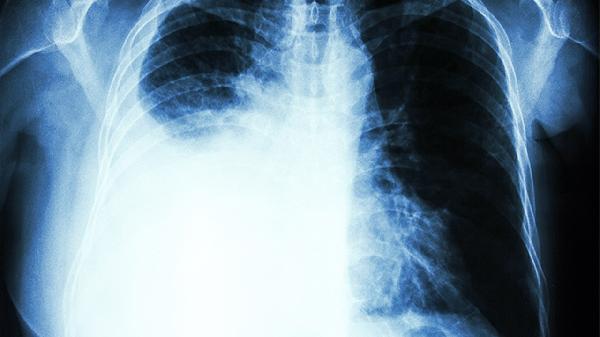

肋骨一高一低考虑是不良姿势导致,也可能与患有肋骨骨折、肿瘤等疾病有关,应根据不同病因选择不同的方法进行治疗。

如果肋骨周围组织出现了肿瘤,当肿瘤不断增大时,会导致局部出现明显肿胀感,使肋骨在外观上看起来,高度会不一致。此时可以在医生指导下通过肿瘤切除术手术方式进行治疗。